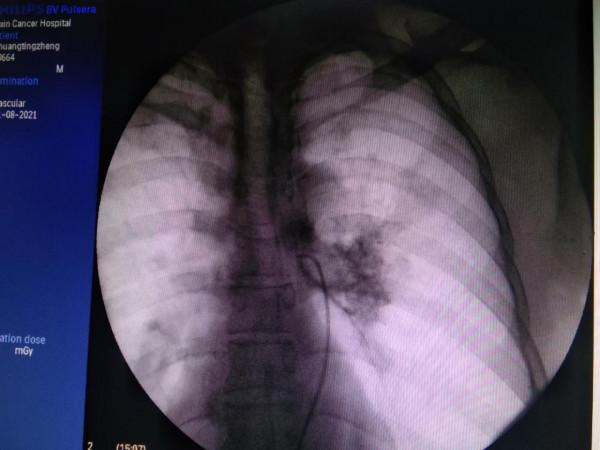

53歲肺鱗癌患者,中央型,咯血,無外科手術機會。

經過MDT會診,行介入動脈灌注化療,兩週期治療後腫瘤消失。